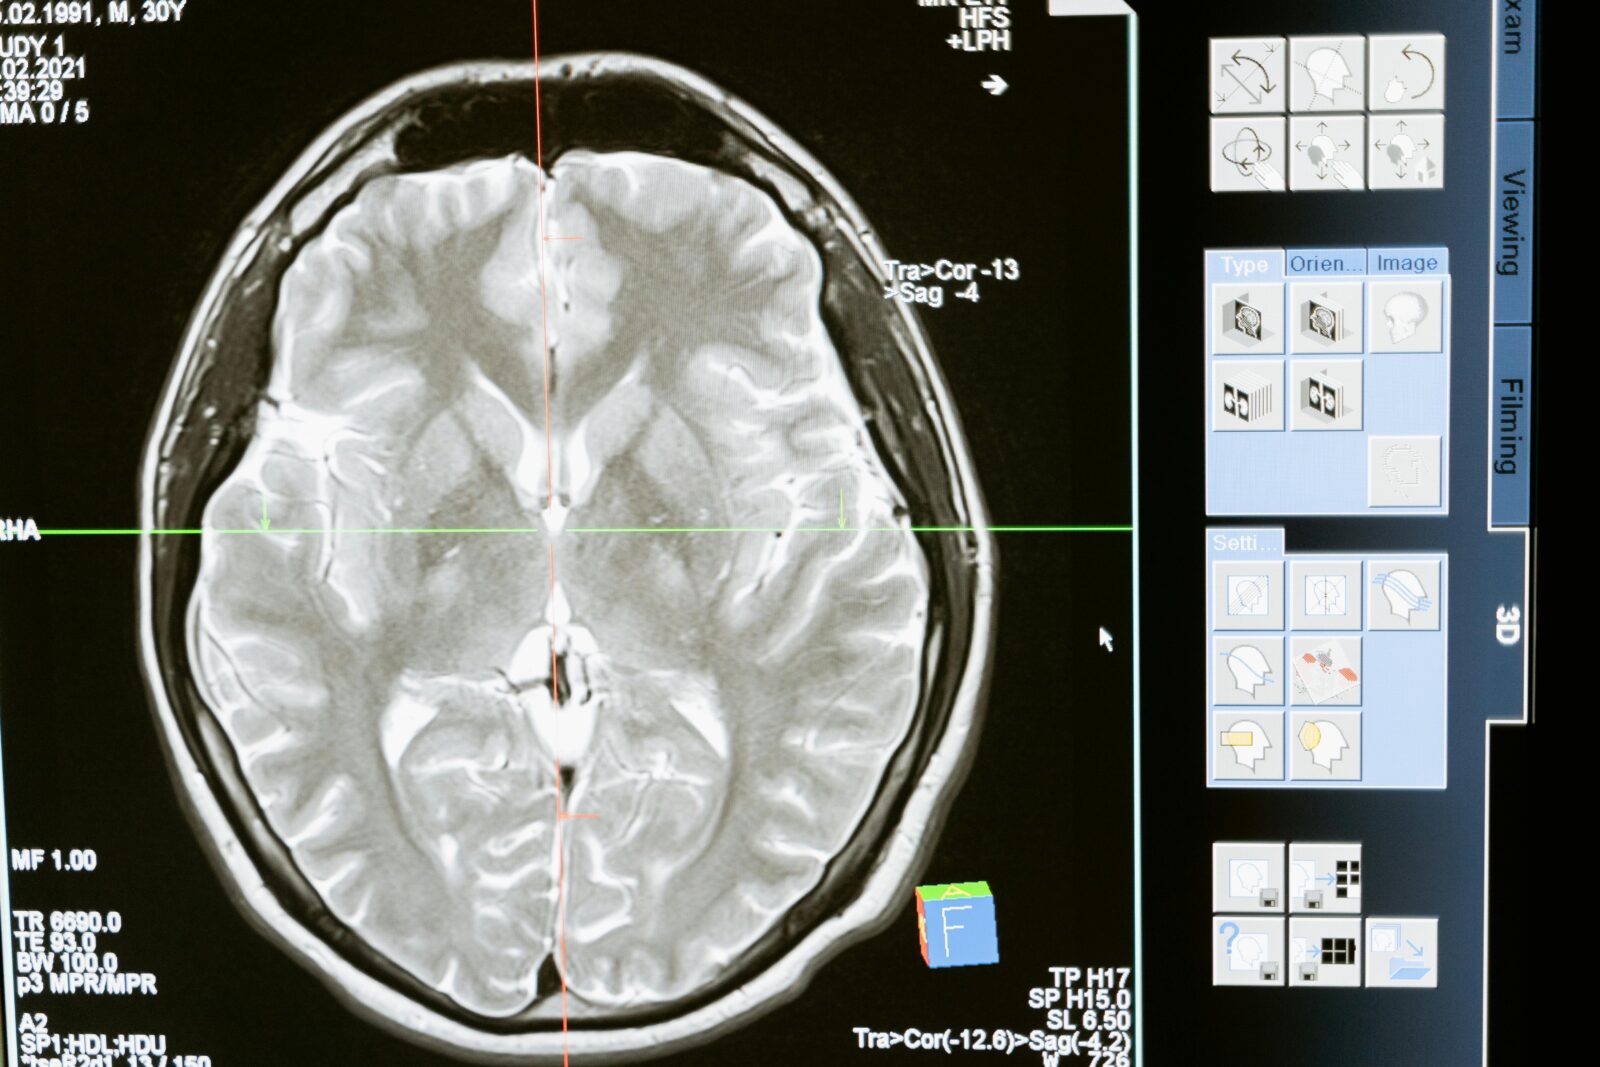

Wearables are evolving beyond fitness tracking to monitor chronic conditions, detect irregular heart rhythms, and even measure blood oxygen levels. Meanwhile, AI algorithms are being used to analyse medical images with accuracy rivalling that of human radiologists.